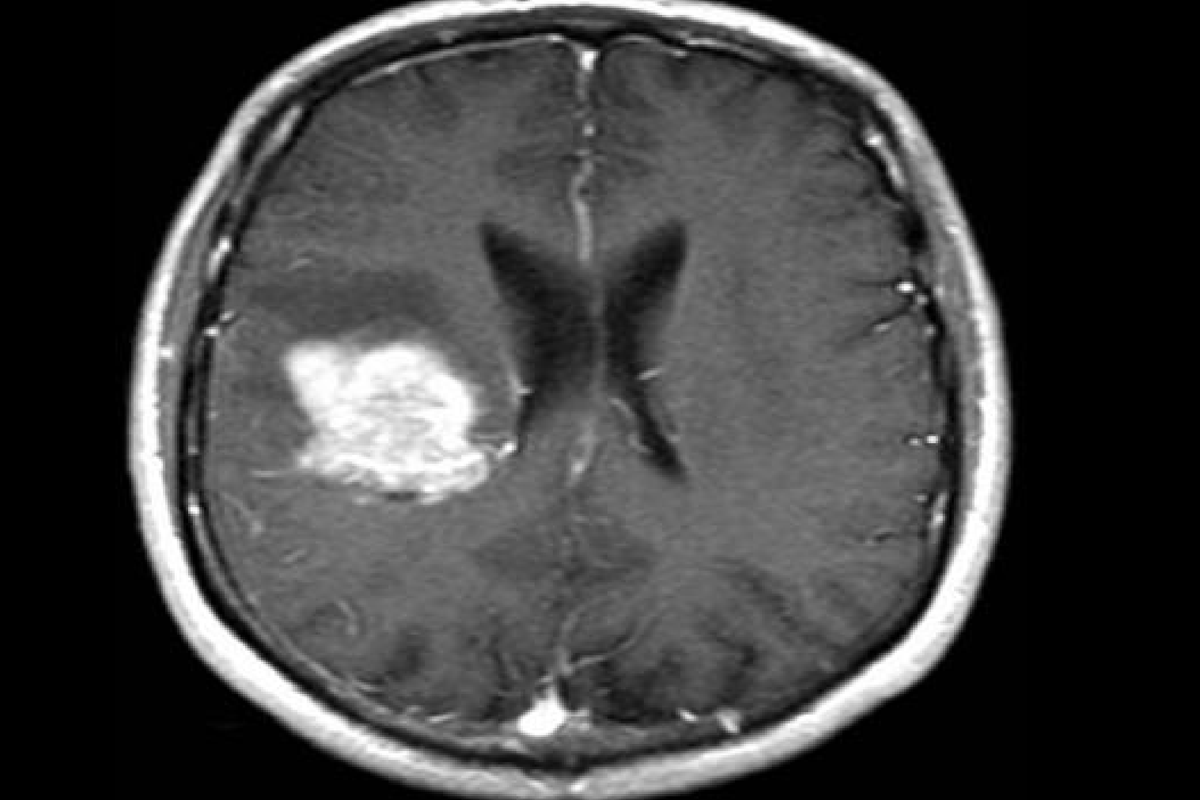

AI shows promise in detecting brain cancer spread